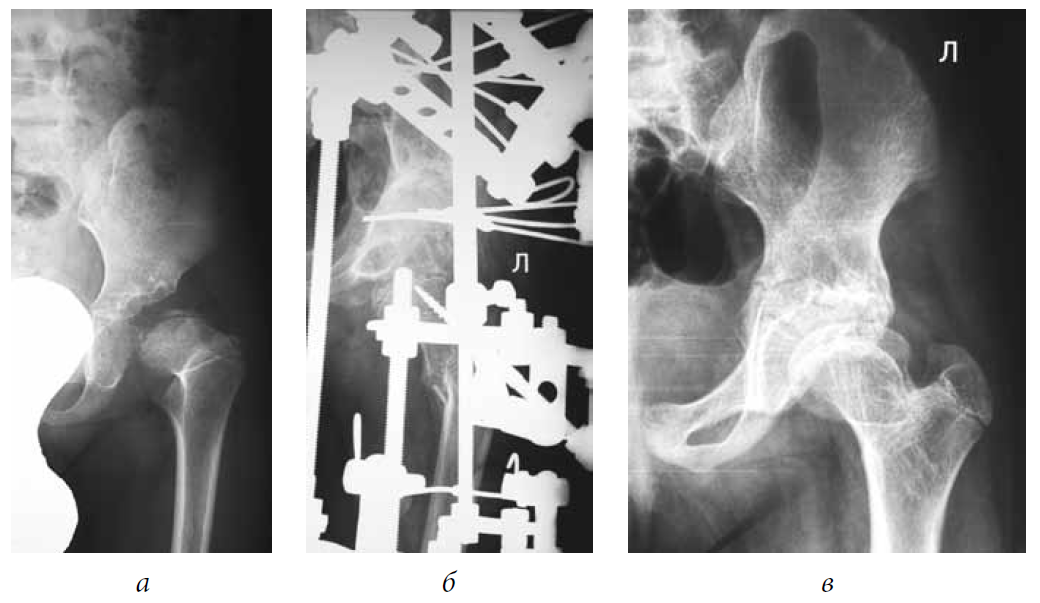

Fig. 1. Patient M., 5 years old, with a diagnosis of subluxation of the left hip, degree II of dislocation, and degree IV Perthes disease: a — frontal radiograph of the hip joint before treatment; b — frontal radiograph of the hip joint during treatment (after tunneling of the femoral neck and head, extra-articular reconstruction of the pelvic and femoral components of the joint, hardware decompression of the joint); c — frontal radiograph of the hip joint 5 years after treatment

Fig. 2. Patient D., 4 years old, with a diagnosis of subluxation of the left hip, degree II of dislocation, and degree II Perthes disease: a — frontal radiograph of the hip joint before treatment; b — frontal of the hip joint during treatment (after tunneling of the femoral neck and head, extra-articular reconstruction of the pelvic and femoral components of the joint, and hardware decompression of the joint); c — frontal radiograph of the hip joint 3 years after treatment